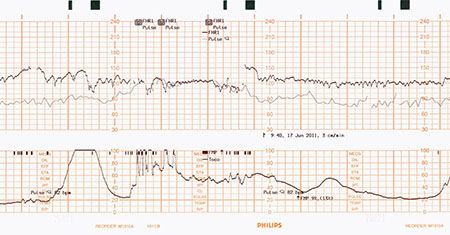

El monitoreo fetal electrónico proporciona información valiosa sobre el estado de salud del feto. Sin embargo, a veces, el pulso de la madre se confunde con la frecuencia cardíaca del feto, un error que se conoce como ambigüedad de la señal de la frecuencia cardíaca materna o inserción maternal. Cuando esto sucede, ciertos problemas del feto pueden pasar desapercibidos.

La tecnología Smart Pulse distingue entre el pulso de la madre y el ritmo cardíaco del feto sin necesidad de un sensor adicional de SpO2 y ECG.

En la mayoría de los casos, el sistema de monitoreo fetal detecta fácilmente la frecuencia cardíaca del feto. En algunos casos, como cuando el feto no tiene frecuencia cardíaca o si un vaso de la madre está sobre el corazón del feto, se puede confundir el pulso de la madre con la frecuencia cardíaca del feto. En especial, cuando la madre está estresada y su pulso se eleva, este adopta una frecuencia similar a la del latido del corazón normal de un feto. Este pulso elevado hace que sea difícil para el profesional de la salud distinguir las señales.

Para evitar la ambigüedad de la señal ocasionada por la frecuencia cardíaca de la madre, los monitores realizan una detección de coincidencias. La detección de coincidencias compara continuamente el pulso de la madre o su ritmo cardíaco, derivado de las mediciones del SpO2 o el ECG, con la frecuencia cardíaca del bebé. Cuando las dos frecuencias coinciden, el sistema de monitoreo alerta al profesional de la salud. Todos los monitores para fetos Avalon de Philips realizan esta detección de coincidencias a través de una característica estándar, llamada verificación cruzada de canales (CCV).

Si bien la detección tradicional de coincidencias es eficaz, requiere que las mediciones de SpO2 y el ECG se realicen con sensores o electrodos independientes. Esto puede ser incómodo para la madre, requiere trabajo adicional para el profesional de la salud y no siempre es parte del protocolo estándar del hospital.

¿Cómo funciona Smart Pulse?

Los médicos deben controlar minuciosamente la frecuencia cardíaca de la madre y del bebé durante el trabajo de preparto y el parto. Por desgracia, a veces, se puede crear confusión al distinguir entre los dos pulsos, lo que genera una situación en la que los médicos no se dan cuenta de que ya no monitorean el corazón del bebé.

Smart Pulse mide el pulso de la madre sin cables, electrodos o sensores adicionales. Esta característica patentada aprovecha el transductor MP Toco, cuyo diseño único mide las contracciones y la frecuencia cardíaca de la madre. El transductor MP Toco tiene dos sensores que miden el pulso de la madre, justo debajo de la superficie de la piel, lo cual evita confundir las señales

La verificación cruzada de canales (CCV) a través del SpO2 o ECG y del Smart Pulse de Philips permite medir el pulso, ofrece mayor comodidad y facilita el uso.